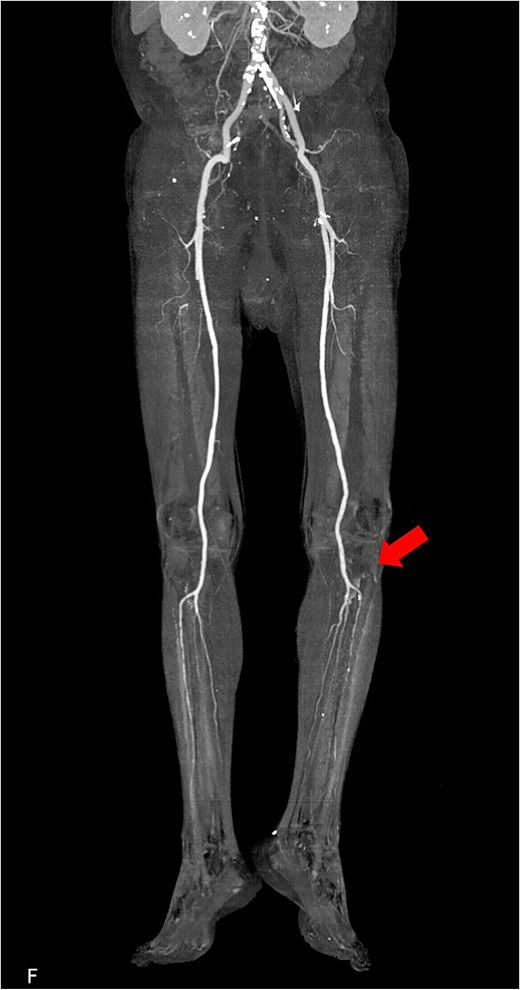

The patient was a 78-year-old man who had been hospitalized at a prior institution for Tolosa-Hunt syndrome, a rare inflammatory condition causing orbital pain. He had undergone steroid pulse therapy and was maintained on oral prednisolone (40 mg daily). He was also receiving medical treatment for diabetes mellitus, with an HbA1c level of 7.9%. The patient presented with complaints of left leg discomfort and weakness. Contrast-enhanced CT revealed poor perfusion distal to the left common iliac artery, leading to a diagnosis of ALI. He was subsequently transferred to our surgical department for further evaluation and treatment. On arrival, physical examination revealed coldness in the left lower limb, with absent palpable pulses in the dorsalis pedis and posterior tibial arteries. Doppler ultrasonography confirmed the absence of arterial flow in the left lower extremity, consistent with critical ischemia. The patient's electrocardiogram showed sinus rhythm. A review of CT imaging showed thrombotic occlusion extending from the left common femoral artery (CFA) to the superficial femoral artery, with poor perfusion distal to the popliteal artery (Video 1) (Fig. 1). Additionally, a filling defect was identified in the distal aortic arch, consistent with a thrombus (Fig. 2a). The thrombus appeared pedunculated and was attached to the lesser curvature of the descending thoracic aorta distal to the left subclavian artery. It was considered highly mobile, posing a significant risk of embolization. No evidence of intracardiac thrombi was observed, and the DTAT was identified as the likely embolic source responsible for the ALI. Given the urgency of salvaging the ischemic limb, thrombus retrieval was prioritized, while simultaneous management of the embolic source was deemed equally critical to prevent recurrence. Open surgery was considered high-risk due to the patient’s age, diabetes, and chronic steroid use. As a less invasive alternative, we opted for TEVAR to immobilize the floating thrombus. During the procedure, bilateral CFAs were surgically exposed to provide access and enable immediate removal of the embolic source if needed. A transesophageal echocardiogram (TEE) revealed a highly mobile intra-aortic thrombus (Video 2). A 26× 26 × 150 mm stent graft (Valiant Captivia Thoracic Stent Graft; Medtronic, Santa Rosa, CA, USA) was deployed just distal to the left subclavian artery under fluoroscopic guidance. Real-time TEE guidance ensured continuous monitoring of the floating thrombus and confirmed no embolization during intravascular manipulation. Following stent graft deployment, thrombus retrieval was performed via the left CFA using a 4-Fr Fogarty catheter (Fogarty Fortis arterial embolectomy catheter; Edwards Lifesciences, Irvine, CA, USA), successfully retrieving fibrin thrombi. Intraoperative angiography demonstrated restored blood flow in the lower extremity, with improved perfusion extending to the foot. Pulses in the dorsalis pedis and posterior tibial arteries were palpably restored bilaterally. The patient was extubated in the operating room and progressed without any findings suggestive of intestinal or lower extremity ischemia. Postoperative CT confirmed successful exclusion of the aortic thrombus (Fig. 2b) and restoration of adequate lower limb perfusion (Fig. 3). The patient was initiated on oral anticoagulation therapy with edoxaban 30 mg to prevent future thrombus formation and experienced an uneventful recovery. This patient has remained free of recurrent embolic events and has shown stable progress post-procedure.

Preoperative 3D reconstructed contrast-enhanced CT. No contrast effect is seen in the blood flow of the lower leg.